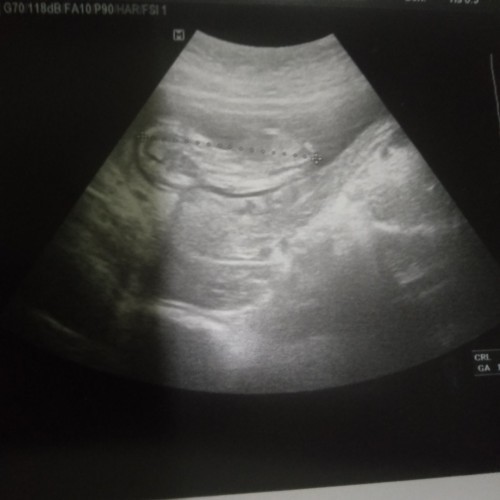

ช่วยดูให้หน่อยค่ะ

แบบนี้ผญ.หรือผช.ค่ะ😂😌

แบบนี้หญิงหรือชายคะ ขอบคุณมากค่ะ

กำลังตั้งครรภ์